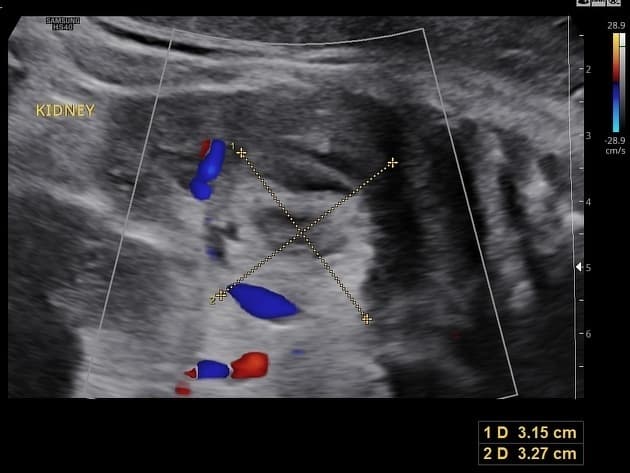

- Khối tròn, ranh giới rõ, kích thước 2,8 cm ở không gian thượng thận phải, có biến đổi dạng nang trong lòng khối. Khối này kề sát nhưng không xuất phát từ cực trên của thận phải.

Khối thượng thận phải này lần đầu được phát hiện trên hình ảnh trước sinh. Chụp hình được lặp lại vào ngày sinh, hình ảnh phù hợp nhất với u nguyên bào thần kinh sơ sinh (neonatal neuroblastoma).

U nguyên bào thần kinh sơ sinh (neonatal neuroblastoma)

U nguyên bào thần kinh sơ sinh là khối u đặc ngoài sọ phổ biến nhất ở trẻ sơ sinh, thường xuất phát từ tủy thượng thận. Bệnh thường được phát hiện trước sinh như một khối thượng thận ranh giới rõ, đôi khi có thành phần nang. Khác với xuất huyết thượng thận bẩm sinh, có thể cho thấy các đặc điểm thay đổi của tụ máu, u nguyên bào thần kinh thường ổn định hoặc phát triển và có thể xuất hiện vôi hóa trên hình ảnh theo dõi. Việc không liên quan đến thận giúp loại trừ các khối u thận nguyên phát như u Wilms. Hầu hết các trường hợp ở trẻ sơ sinh là giai đoạn thấp và có đặc điểm sinh học thuận lợi, tỷ lệ tự thoái lui cao, đặc biệt ở trẻ dưới 6 tháng tuổi. Việc định hình sớm bằng hình ảnh và theo dõi là chìa khóa để tránh các can thiệp không cần thiết.